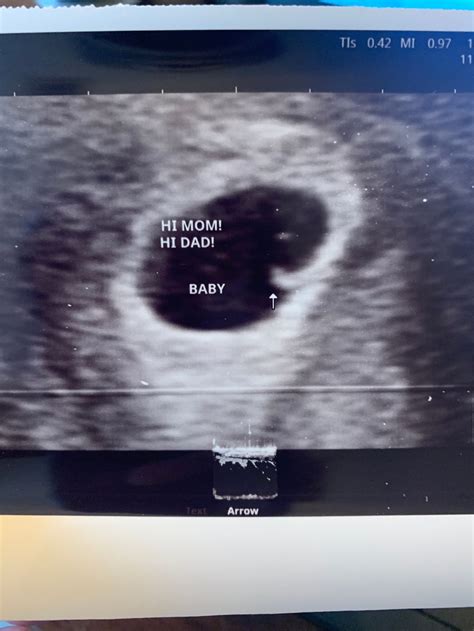

7 Week Ultrasound

Embarking on the journey of parenthood is an exciting and transformative experience. One of the most anticipated milestones during pregnancy is the 7 week ultrasound. This early scan provides crucial insights into the development of the embryo and helps ensure a healthy pregnancy. Understanding what to expect during this ultrasound, its significance, and how to prepare can alleviate anxiety and enhance the overall experience.

The 7 week ultrasound is typically performed transvaginally, which involves inserting a probe into the vagina to get a clearer image of the uterus and the developing embryo. This method is particularly useful in the early stages of pregnancy when the embryo is still very small. The ultrasound can detect the gestational sac, yolk sac, and fetal pole, which are essential indicators of a healthy pregnancy.

During this scan, the sonographer will look for several key indicators:

• The gestational sac: A fluid-filled structure that houses the embryo.

• The yolk sac: A small sac that provides essential nutrients to the embryo.

• The fetal pole: The earliest visible part of the embryo, which will eventually develop into the fetus.

• Heartbeat: Although it may be too early to detect a heartbeat at 7 weeks, some advanced ultrasound machines can pick up the fetal heartbeat around this time.